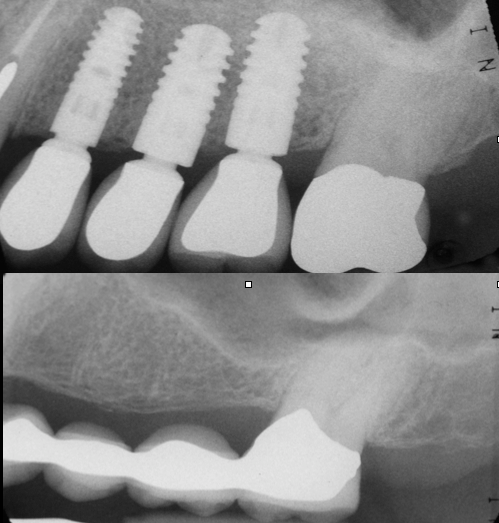

Fractured Tooth Ankylos Implant X-ray

Ankylos Implant X-ray Results

Before (top)

After (bottom)